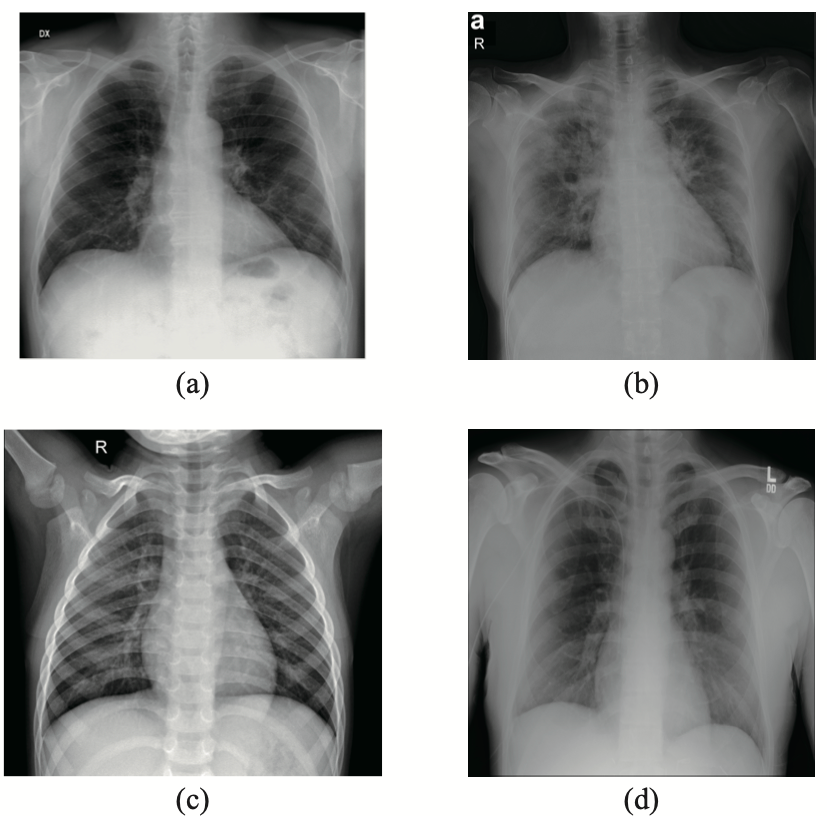

Throughout the COVID-19 pandemic, chest CT has gotten the most attention as the imaging option for detection, but a new study shows that, when paired with artificial intelligence (AI), chest X-ray can provide near-perfect identification, potentially leading to clinical benefits in the future.

But, to determine how effective AI-fueled chest X-rays are at detection, the team only had 194 publicly available COVID-19 X-rays and 194 X-rays from healthy individuals. To compensate for the small amount, they used a model previously trained on a large dataset of other X-rays and trained it to use strategies to identify which lungs were infected with the virus. The top two machine learning methods provided those levels of near-perfect accuracy.